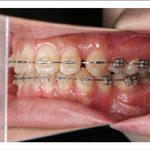

2) 矯正中の状態

![]() |

||